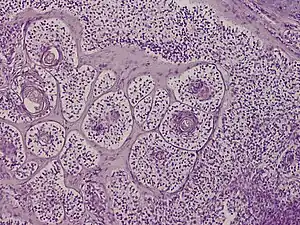

Trichilemmal carcinoma

Trichilemmal carcinoma is a cutaneous condition reported to arise on sun-exposed areas, most commonly the face and ears.[1]: 674